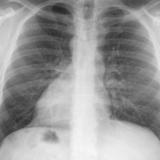

ASD 1 PA

Date: 03/17/2004

Views: 2762